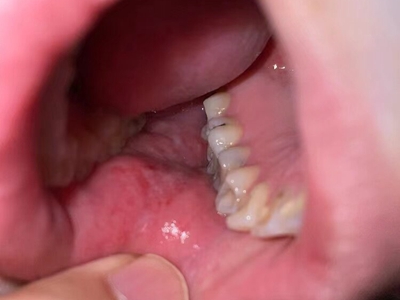

口癣症状图片

口癣的临床特征为口腔黏膜损害,主要为珠光白色条纹或网纹,也可为单线条或绕成环形。在舌背多为圆形或椭圆形白色斑块,损害区乳头消失而平伏。软腭或其他部位可发生透明颗粒状水疱。条纹之间的黏膜色泽可以正常或充血;有时在损害范围内某一区域发生糜烂,在唇部或颊黏膜处有时可出现针头大小、微隆的丘疹。